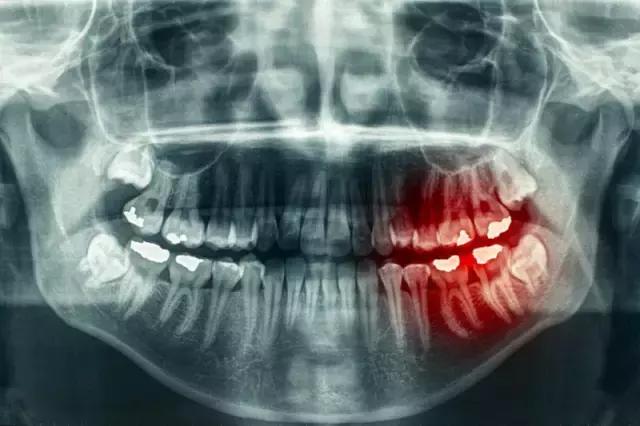

不少人有过这样的体验,当遇到酸甜冷热食物的刺激,牙根就会突然酸痛难忍,不敢咀嚼,俗称“倒牙”,医学上称为牙本质过敏症。其实,牙本质过敏不是病,它是一个症状,是牙齿上暴露的牙本质部分受到机械、化学或温度刺激时,产生的一种特殊疼痛症状。

牙本质过敏症好发于牙齿磨耗严重的部位及牙颈部,可以发生在一个或多个牙上。刷牙、吃硬物、酸、甜、冷、热等刺激均可引起牙酸痛,刺激去除后症状即消失。医生用尖锐的探针在牙面上可探及一个或数个过敏点,或找到一个或数个过敏区,那里可以引起病人特殊的酸、软、疼痛症状。